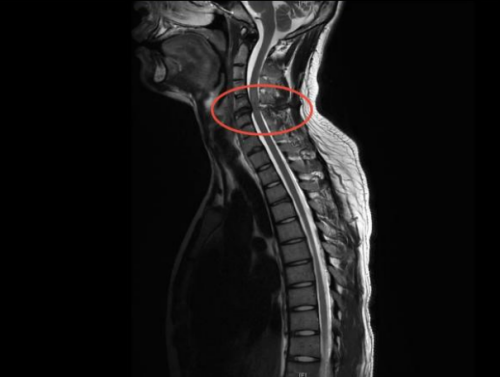

核磁检查提示颈4-6节段脊髓损伤

“影像学检查结果显示,刘琦的颈髓在第4至第6节段出现了严重的挫伤情况,这种损伤属于高位颈髓损伤范畴。”在急诊科,接诊的医生对刘琦进行了详细的体格检查,发现他的双下肢完全丧失了活动能力,肌力评级为0级,而双上肢仅能进行轻微的移动,肌力评级为3级,乳头平面以下的皮肤感觉完全消失,这些临床表现均为典型的高位颈髓损伤症状。基于这些检查结果和临床表现,医生最终诊断为“颈部脊髓损伤伴随不完全性四肢瘫痪”。